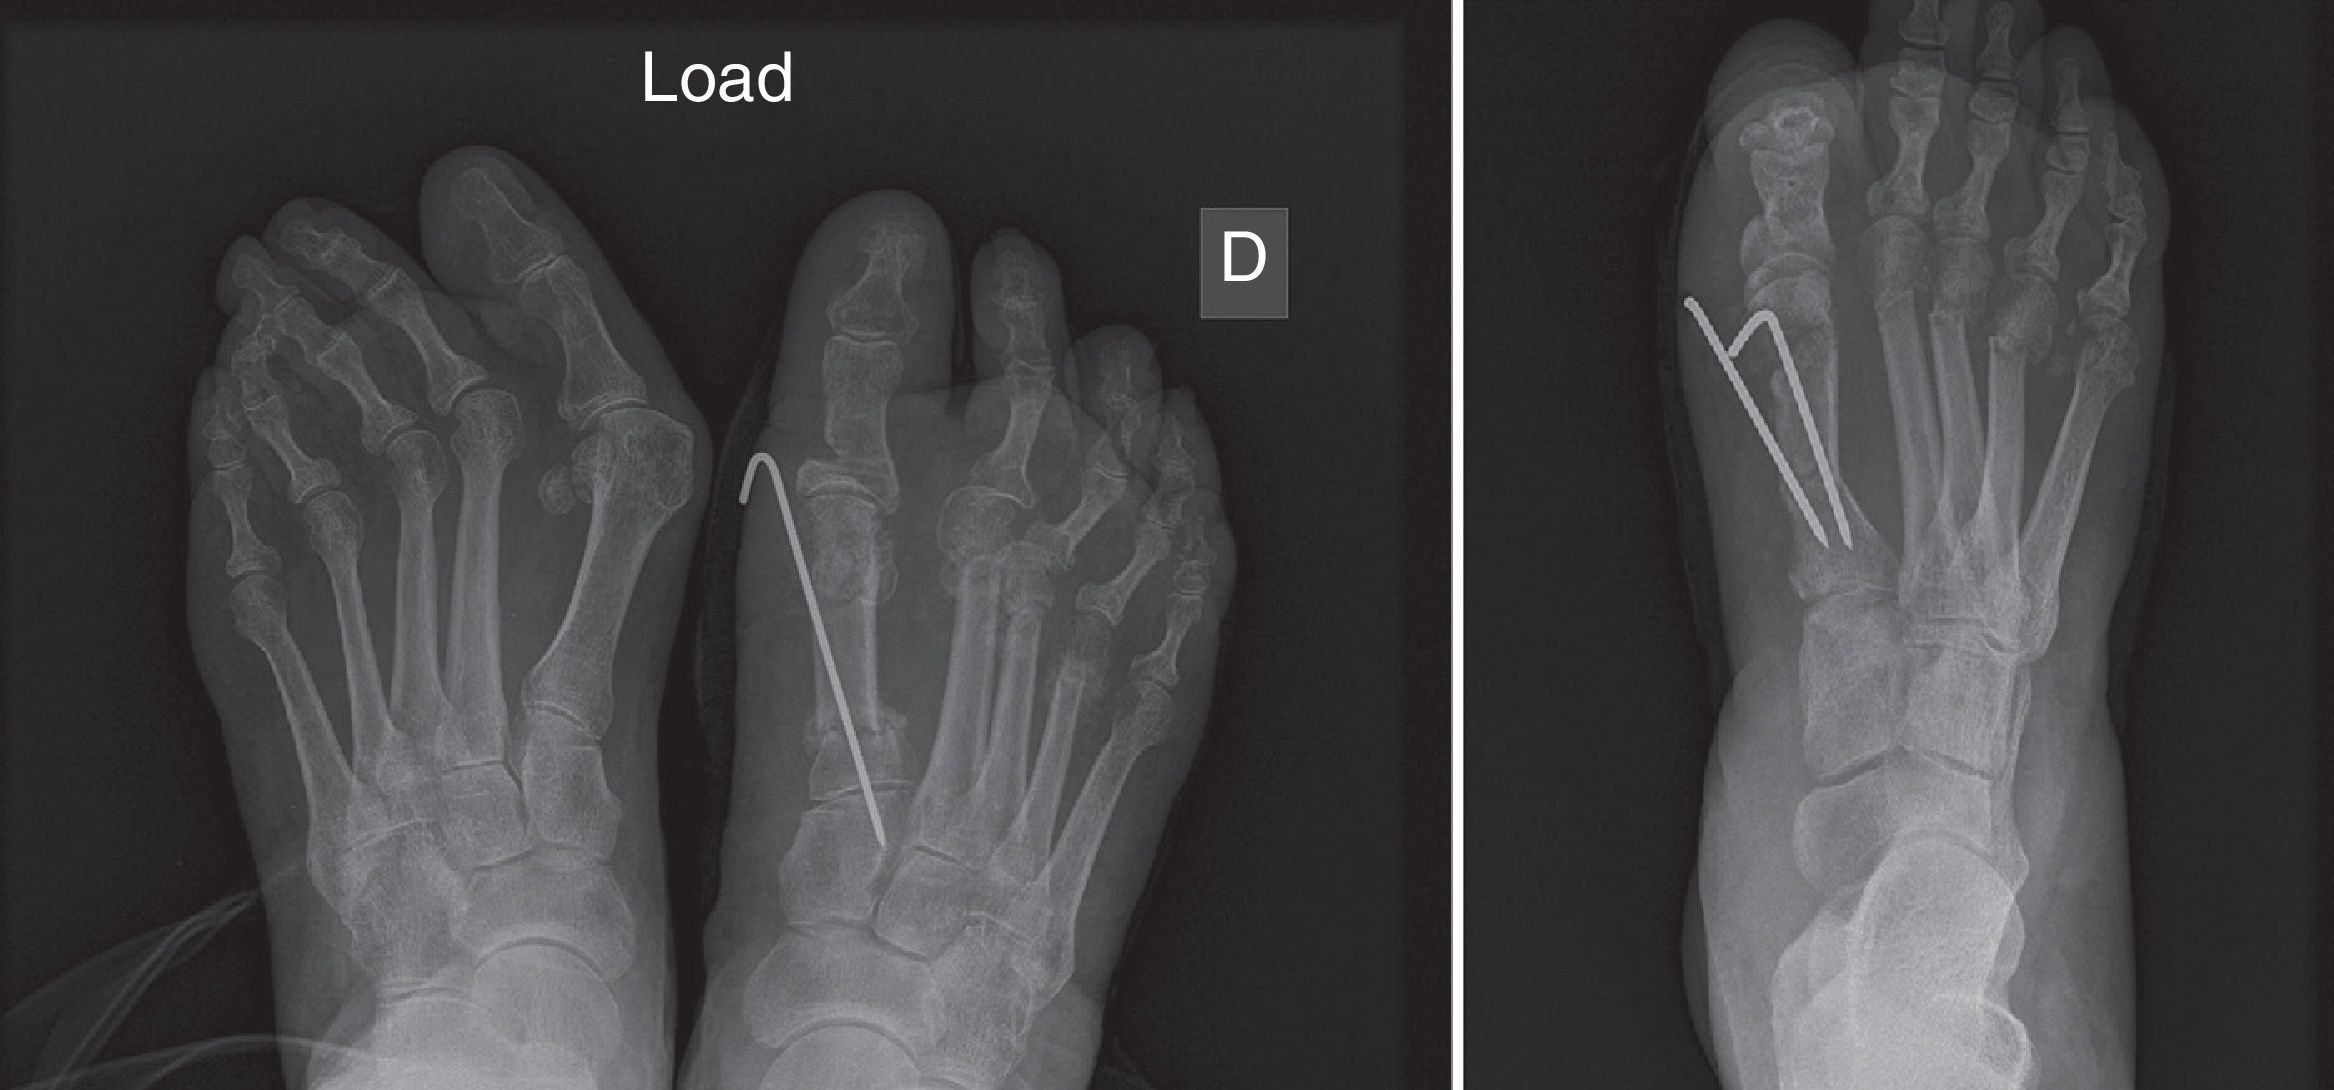

eb4acaabee778636e6a97f8010df93。大腿骨頸部骨折の手術【手外科・外傷】 | おおさかグローバル。Frontiers | Impact of Periosteal Branches and Septo。「大腿骨近位部骨折 : 大腿骨頚部・転子部・転子下骨折の手術手技」高平 尚伸 / 最上 敦彦 / 神田 章男 / 北田 真平定価: ¥ 14000#高平尚伸 #高平_尚伸 #最上敦彦 #最上_敦彦 #神田章男 #神田_章男 #北田真平 #北田_真平 #本 #自然/医療・薬学・健康 サージカルテクニック裁断済みです。裁断にご理解頂ける方のみご購入よろしくお願いします。Treatment of moderate and severe hallux valgus by performing。書き込みは見たところございません。ペリー 歩行分析 正常歩行と異常歩行。アシックス やり投げ ジャベリンプロ3。